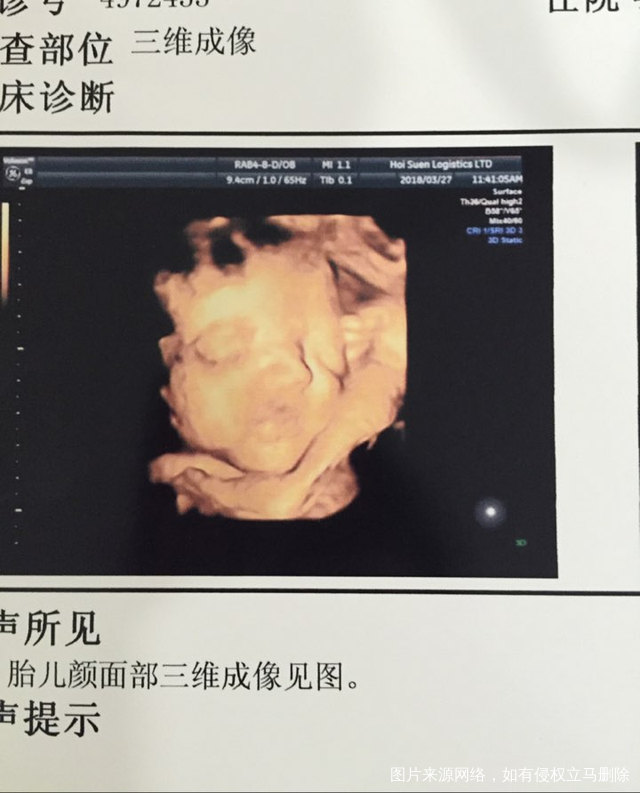

折腾一上午,还好没拿手挡眼睛,[偷笑],第一感觉就是好丑,鼻子和嘴巴都分不清,后来越看越喜欢,这尖下巴,一看就是随了我,果然老公是别人家的好,孩子还是自己的好。